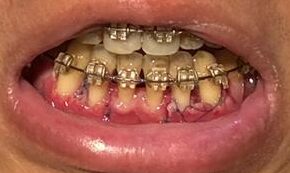

左(上)から:術後5時間後、術後17時間後、術後1週間後、術後3週間後

左(上)から:術後3時間後、術後19時間後、34時間後、58時間後、65時間後、89時間後、114時間後、154時間後

・2026年2月21日撮影

・2025年9月13日撮影

・2022年10月1日撮影(約3年前)